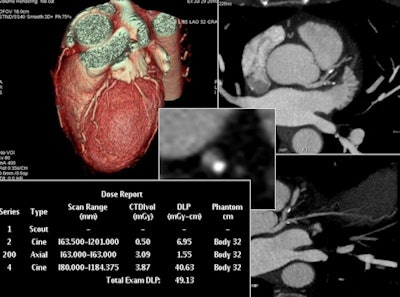

In the final part of the study, Matkevich et al analyzed the image quality of low-dose CT examinations of the heart and coronaries, chest, and carotids. According to the authors, good diagnostic quality was maintained despite a reduction in radiation exposure, this achieved with decreased tube voltage (80 kV to 100 kV) and tube current in combination with iterative reconstruction (ASIR and MBIR).

Low-dose CT for complex scanning is increasingly feasible, thanks to decreased tube voltage and current, in combination with iterative reconstruction, according to Sinitsyn. This reconstructed image from low-dose coronary CTA was achieved with reduced tube voltage of 80 kVp and automatic tube current modulation.He explained the department website regularly received letters from worried patients, particularly women, who typically discover postscan they were already pregnant when undergoing the exam. The Moscow group wanted to show that radiation exposure from CT in the hospital was compatible with levels in other countries and within acceptable limits.